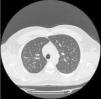

Our patient was a 36-year-old man, employed for the last 20 years in the cutting of ornamental rock (continuous occupational exposure to quartz, granite, marble, etc.), and an active smoker of 5 pack-years. He consulted with a 1-year history of episodes of arthritis in the elbows, wrists and proximal interphalangeal joints, with morning stiffness and limited hand flexion, which improved throughout the day. This was accompanied a 1-year history of dyspnea on moderate exertion and dry mouth and eyes. Physical examination revealed inflammation and swelling of the proximal interphalangeal joint, wrist and left elbow. Pulmonary auscultation was normal. Clinical laboratory tests showed raised acute phase reactants (ESR 35mm and CRP 25mg/l) and strongly positive anti-Ro and anti-La. Other parameters (ANA, rheumatoid factor, and anti-citrullinated protein antibodies) were negative. Schirmer's test was positive (3mm) and salivary scintigraphy showed moderate-to-severe hypofunction of the parotid glands and submaxillary glands. Chest computed tomography (CT) (Fig. 1) revealed the presence of mediastinal and hilar lymphadenopathies and a diffuse micronodular pattern in the upper fields. Respiratory function tests (spirometry, plethysmography, diffusion, and walk test) were normal. The patient was given a diagnosis of silicosis and SS, and, in view of the intensity of his arthritis, treatment began with tapering doses of prednisone and hydroxychloroquine, with subsequent improvement.

Another aspect to bear in mind is that the prevalence of lung disease in SS, defined as the presence of symptoms or functional changes, ranges from 9% to 22%, or close to 50% if subclinical disease is taken into consideration.11 The spectrum of pulmonary manifestations of primary SS covers three groups: airway abnormalities (bronchiolitis, bronchial hyperreactivity, and bronchiectasis), interstitial lung disease (non-specific interstitial pneumonia, usual interstitial pneumonia, chronic lymphocytic interstitial pneumonitis, and organizing pneumonitis), and another miscellaneous group (pulmonary lymphoma, amyloidosis, pulmonary hypertension, and pulmonary thromboembolism).12 Our case showed the classic manifestation of simple silicosis: diffuse bilateral nodular pattern, predominantly in both upper lobes.